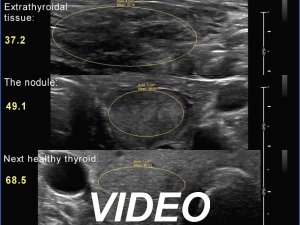

Ultrasonography. The thyroid was partly minimally/moderately, partly very hypoechoic. There was a nodule in the middle of the left lobe. It was lighter than the extranodular part but darker than a normal, healthy thyroid.

Comments. All but one society suggest to compare the nodule' echogenicity to the non-nodular part. In this case, the nodule should be regarded as iso/hyperechoic. If we accept the suggestion of the 2023 ETA guideline, then we should consider the nodule as minimally/moderately hypoechoic because the reference tissue in the ETA is the normal, healthy thyroid and not the diseased, extranodular part.